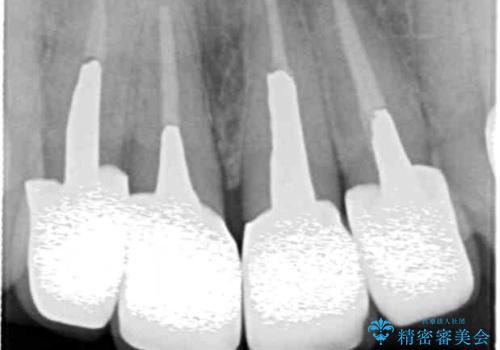

X線写真より問題のなかった根管治療は行わず、クラウンを除去し仮歯でを装着したのちジルコニアクラウンを製作していきます。

失活歯の治療について

神経をすでに取られている歯の治療を行う場合、コアを除去したのちの再根管治療を行う場合とクラウンのみやり替えする場合、状況に応じて適切な治療をご提案いたします。